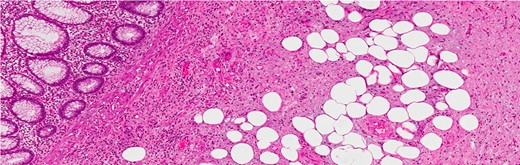

Histological examination showed an appendix measuring 7 cm in length and 0.8 cm in diameter with a cystic lesion at the base measuring 3.5 × 2.5 cm2. It had a grey homogenous cut surface invading the appendix wall while the mucosa was unremarkable. The mucosal lining showed elongated and dilated tubules with Goblet cell proliferation with no evidence of dysplasia. The sub-mucosa displayed an area of extensive edema, vascular congestion with focal hemorrhage and abundance of spindle cells, dispersed in a loose fibromyxoid stroma. The sub-mucosal background had copious eosinophils, lymphocytes and blood cells. There was no mitosis, acute inflammation, granuloma, ischemia or vasculitis (Figs 3–6). These findings are consistent with an appendicular IFP (Vanek’s tumor).

The tip and the middle part of the appendix with no specific pathology (H&E stain, low power).

The base of the appendix with the mass (H&E stain, low power).